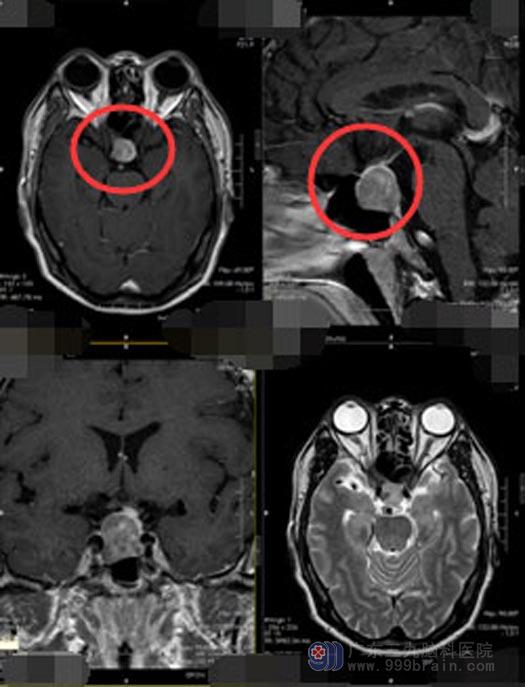

最近几个月,潘大哥在血压控制正常的时候也会出现头晕头痛症状,这引起了他的警觉。当地医院头颅MR提示“鞍区占位性病变,考虑垂体瘤可能”。由于当地医院医疗水平有限,吓坏了一家子人经过多方打听,找到了广东三九脑科医院垂体瘤诊治中心。经过进一步的检查,也同样考虑是垂体瘤可能。

脑垂体瘤的治疗刻不容缓,经鼻蝶手术是最佳的治疗方案,该手术具有创伤小,并发症少,恢复快等特点。得到潘大哥和家人的同意后,垂体瘤诊治中心的手术团队为他实施了“内镜经鼻蝶鞍区垂体腺瘤切除术”。手术过程很顺利,肿瘤被完整的切除。

▲手术前